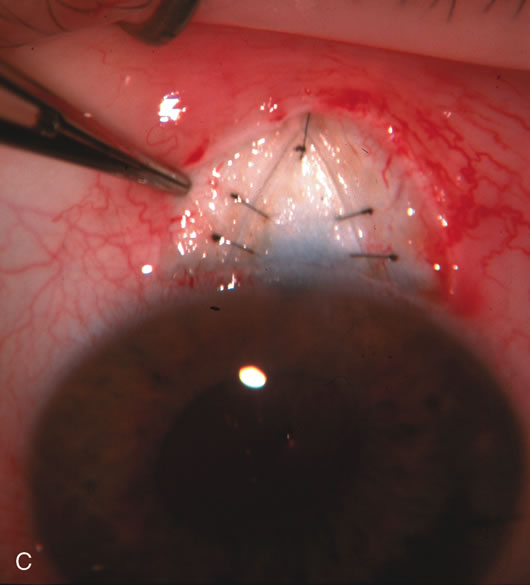

Fig. 7. Phacotrabeculectomy adjacent to a failed filter in cataractous eye. The ability to combine small-incision cataract extraction with trabeculectomy all through the same incision adjacent to the failed filter allows the surgeon to work in a familiar superior area. Avoiding incisions into the existing bleb decreases conjunctival buttonholes, hypotony, operating room time, and subconjunctival bleeding. A. Appearance of failed bleb with exposure of superior temporal quadrant gained with a corneal traction suture. B. Prepare a limbus-based conjunctival flap and a scleral flap. C. This bleb is at high risk to fail again justifying the need for MMC, 0.2 mg/cc applied on a pledget for 4 minutes. D. Insert the keratome and perform phacotrabeculectomy in the usual fashion.